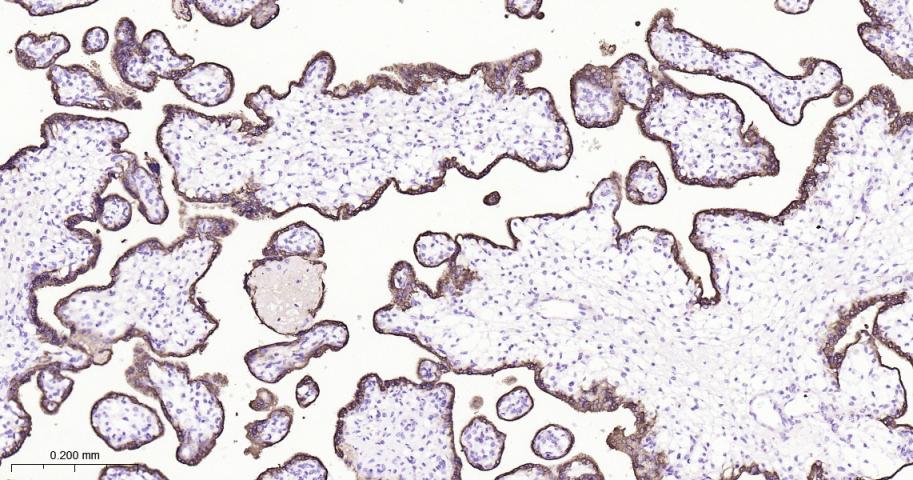

Paraformaldehyde-fixed, paraffin embedded Human Placenta; Antigen retrieval by boiling in sodium citrate buffer (pH6.0) for 15 min; Antibody incubation with GH1 Monoclonal Antibody, Unconjugated(bsm-61438R) at 1:200 overnight at 4°C, followed by conjugation to the bs-0295G-HRP and DAB (C-0010) staining.